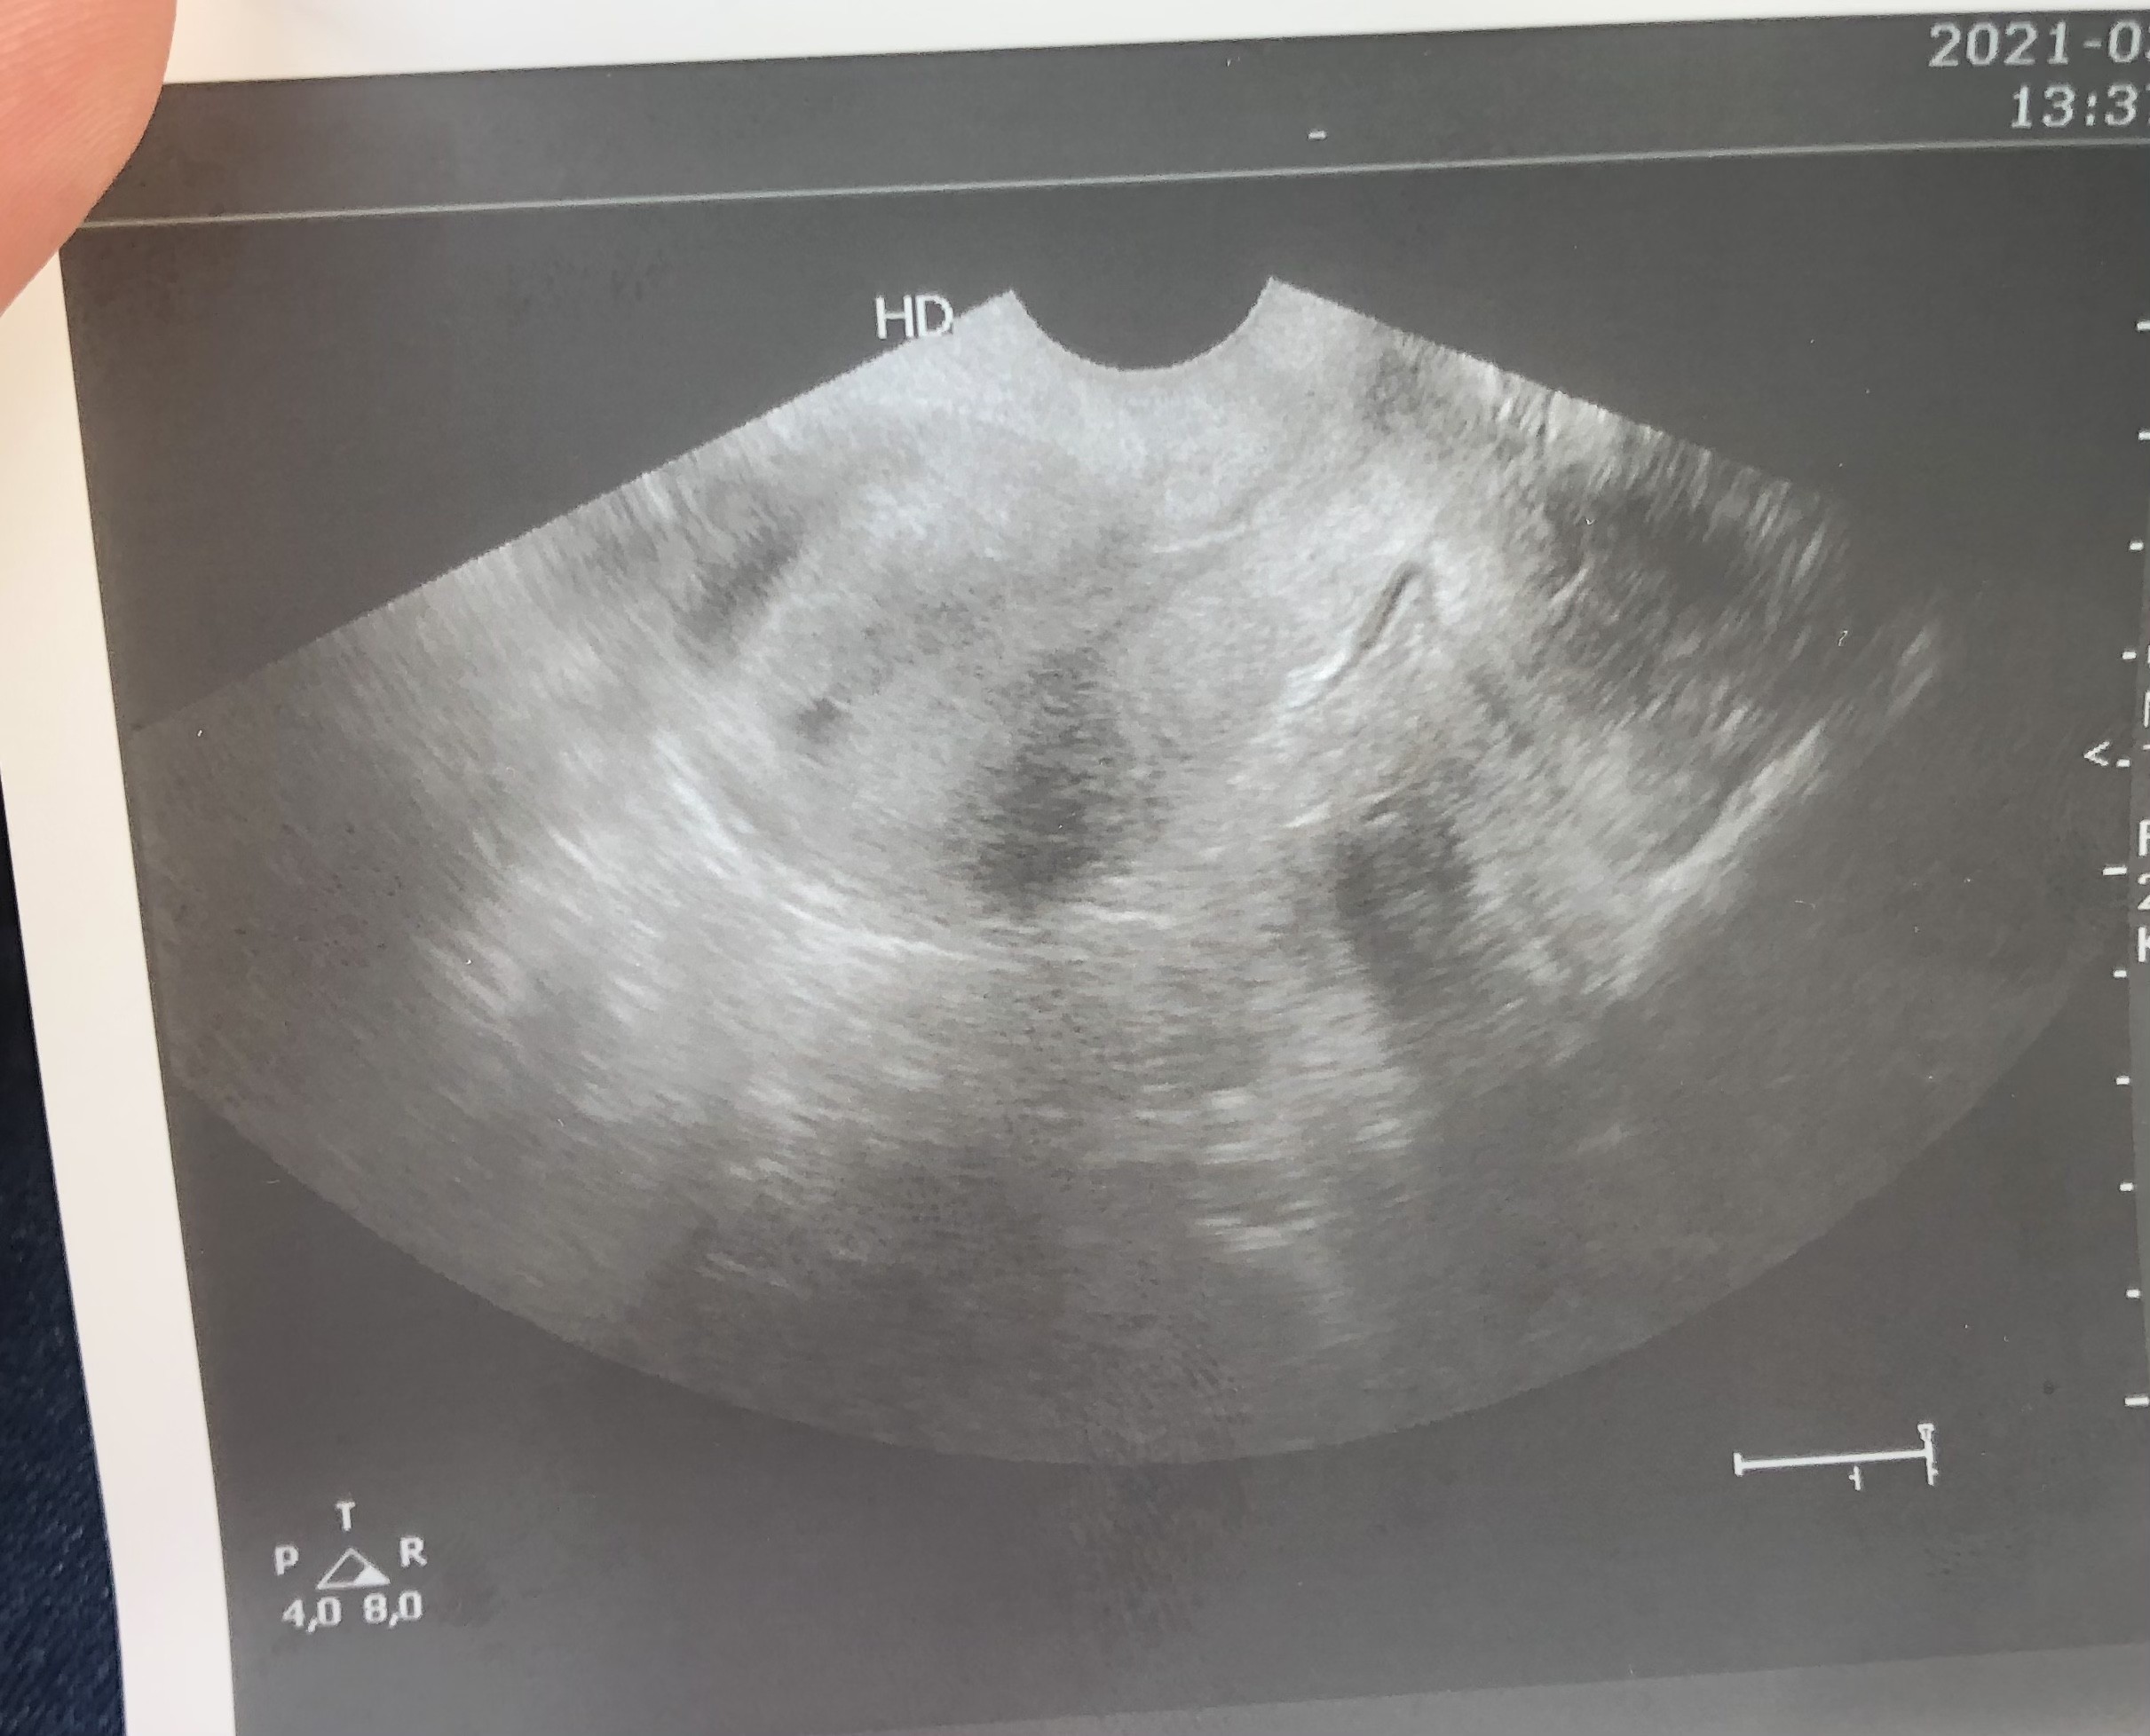

Dziewczyny czy Wy tu widzicie dwa pecherzyki? Doktor coś wspomniała, ze może są dwa, ale pewna jest tylko tego okrągłego. Ten obok chyba nie jest pęcherzykiem? Jak to u Was wyglądało w tym tygodniu? Beta rośnie o 300% co 48 h, wiec przyrost spory, ale w normie.

• 7C9EECD2-62F7-4B40-BB37-04325F75F4D0.jpeg

7C9EECD2-62F7-4B40-BB37-04325F75F4D0.jpeg

528,2 KB · Wyświetleń: 173